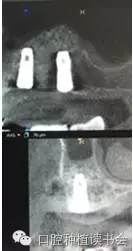

2、經(jīng)側(cè)壁開窗分離粘膜抬高竇底的方法稱為外提升(Lateral Window Technique)。早期由Philip?Boyne提出,后來上頜竇側(cè)壁開窗在粘膜和竇底之間進(jìn)行骨增量的術(shù)式逐步應(yīng)用開來。側(cè)壁開窗后是否同期植入種植體,根據(jù)RBH,種植體穩(wěn)定性的預(yù)判而決定??偟膩碚f,上頜竇外提升術(shù)的成功率86%~100%(Jensen,2009)。根據(jù)CBCT圖像,不但可以提供術(shù)前的種植計(jì)劃指導(dǎo),而且上頜竇外提升術(shù)后的效果,尤其是檢查種植體腭側(cè)是否有植骨不全,都會一目了然。(圖10-12)